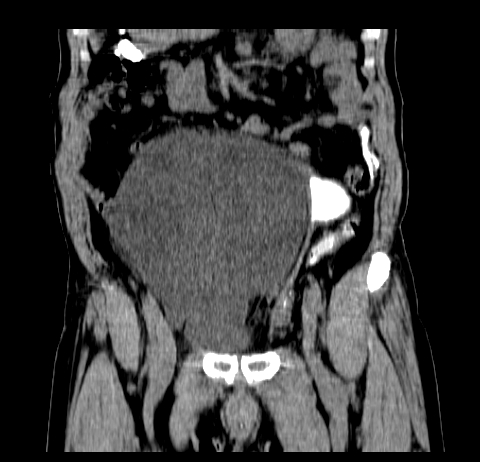

标题: CT19729B:男,74岁,因腿疼就诊,查体触腹部肿物,

增强扫描

静脉期

【ct表现】

1、肿块巨大,往往位于腹膜后,长大后才引起症状而就诊;那么位于腹膜后的肿瘤80%为恶性肿瘤。

2、实性肿瘤,增强扫描轻度不均强化,实性肿瘤一般不是好东西。

3、肿瘤边缘似见少许脂肪样密度。

4、腹膜后未见肿大淋巴结,但肿瘤于临近的肠管及组织接触紧密。

【诊断】

腹部占位,考虑位于腹膜后的恶性肿瘤,脂肪肉瘤(实体型)可能性大。

术后病理结果:腹膜后脂肪肉瘤。